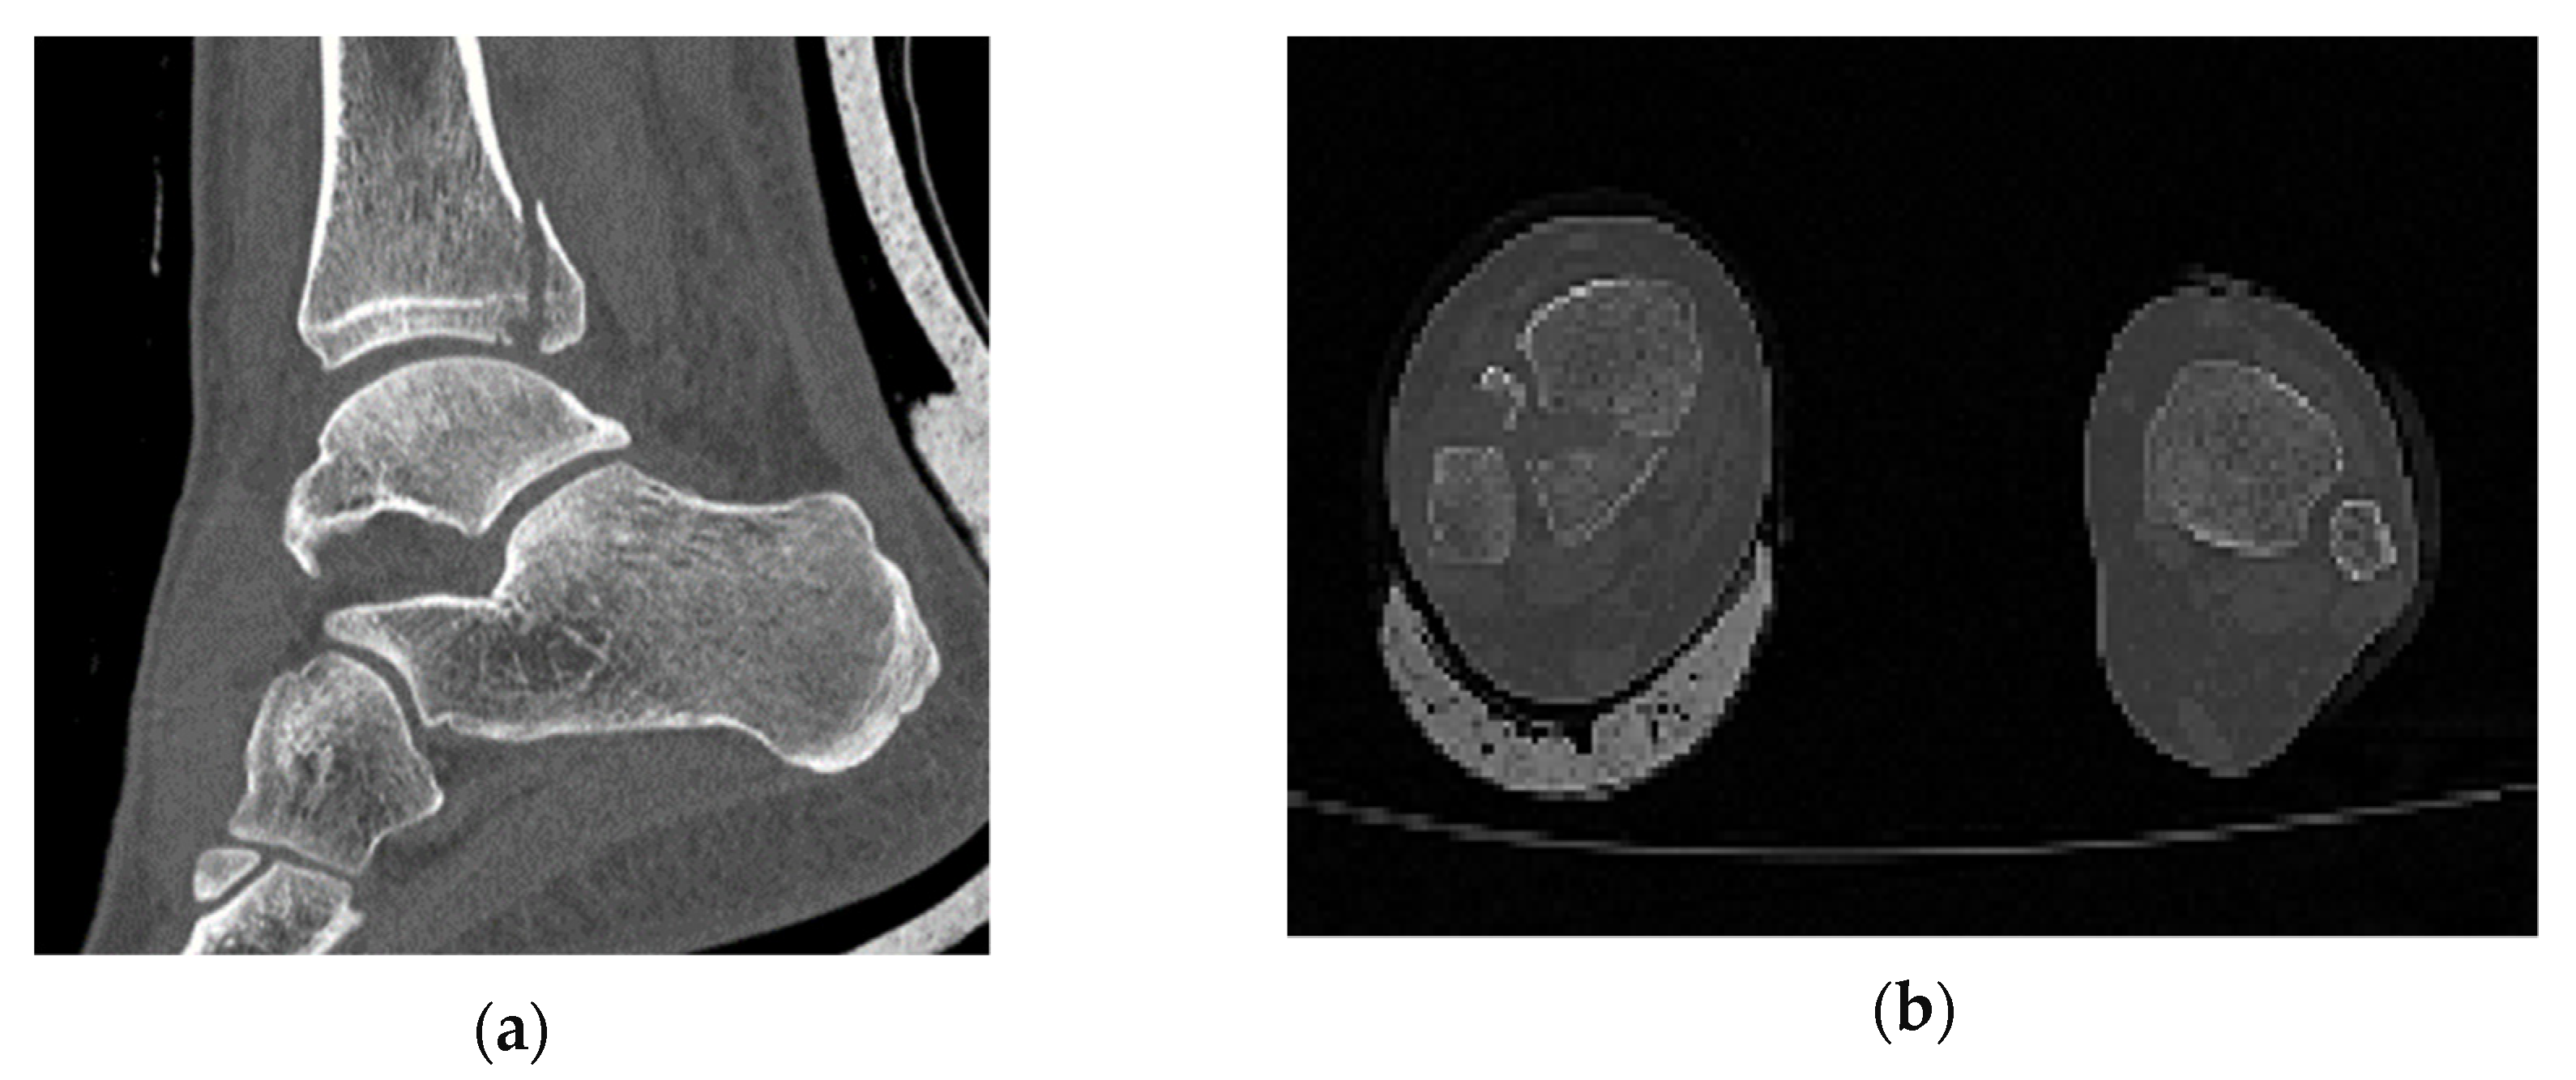

3.2. Mechanical Behaviour of the Bone

The model of the bone with no treatment fixation applied is delivered to unveil where the maximum stress is concentrated and the dislocation of it under action. It is common in finite element models for the stress to be concentrated where the load is applied. To find and point out the maximum stress, ignoring this local phenomenon, we hide those few elements. The maximum von Mises stress is 196.2 MPa and is found where the two parts of the examined bone are connected. The lack of stability in the system shows the necessity of fixation. The way that the bone tents to split (Figure 6) indicates how the treatment solution should be applied, resisting the separation of the two bone parts. The position where the higher stress is found is highlighted (Figure 7).

Figure 6. Dislocation of the bone in different perspectives (scale factor 1000).